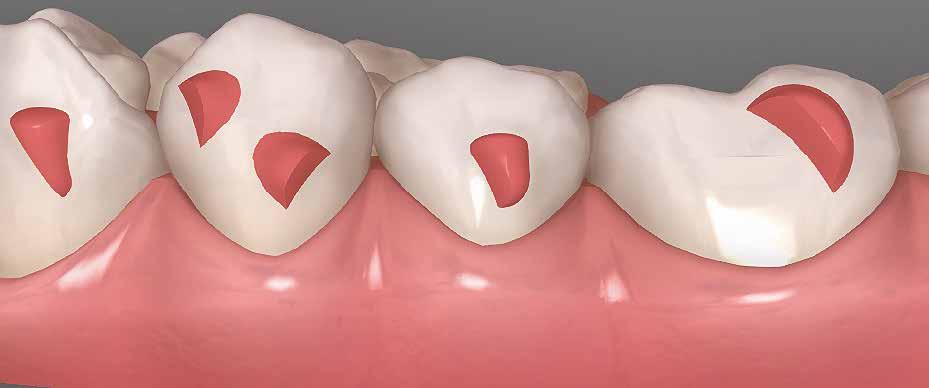

A hiányzó oldalsó kismetszők részárással történő kezelése során a szemfogak és oldalsó fogak meziális mozgatása közben a fogszabályozó orvosnak csiszolással kell a fogak formáját igazítani. Már a kezelés elejétől a szemfog elcsiszolása nem csak az incizális részre kell hogy kiterjedjen, hanem az approximális, palatinális és a vesztibuláris felszín éli negyedére is. Így érhetünk el egy rövidebb klinikai koronát, a vesztibulo-orális méret csökkenését, egy incizális élet, valamint a szemfog megfelelő pozicionálását a kismetsző helyén. A túl széles szemfog megakadályozza a megfelelő interkuszpidáció kialakítását az oldalzónában. A palatinális felszín elcsiszolásával biztosítjuk az interferenciák nélküli metszővezetést, és a megfelelő overjetet a frontfogak enyhe érintkezésével. Ha a szemfogra a későbbiekben esztétikai pótlás készül, a megfelelő approximális elcsiszolás (az esztétikai fogorvossal történő egyeztetés után) biztosítja a zenith kívánatos pozícióját a későbbi felépítéshez. A mezializált kisőrlő palatinális csücskének elcsiszolására csak akkor van szükség, ha ez akadályozza a megfelelő fogérintkezést. Az első kisőrlő mindkét csücske fontos a már a szemfog helyén álló fog esztétikai és funkcionális beállításához.

A szemfog oldalsó kismetsző helyére történő bemozgatása során a fog átalakítása javasolt a két fog eltérő morfológiai adottságai miatt (1. a-b. ábra). A fog kontúrozása, vagy úgynevezett formázása magába foglalja az approximális felszínek elcsiszolását, valamint a többi fogfelszín igazítását a kívánt fogformának megfelelően [1].

A kismetsző és szemfog klinikai koronái közötti eltérések a következőek: mezio-disztálisan keskenyebb oldalsó metsző, csücsök hiánya, egyenes éli lefutás, és a vesztibuláris felszín domborulata is kevésbé kifejezett [2,3]. A szemfoggal összehasonlítva, az oldalsó metsző rendszerint rövidebb és keskenyebb mind mezio-disztálisan, mind vesztibulo-orálisan. Az átformázott szemfog és az oldalsó metsző anatómiai alakja közötti egyezés függ az elülső zóna mint egység formájától is. Kataoke és Nishimura három alapformát határozott meg az elülső fogak tekintetében: négyszögletes, óvóid és háromszög formájú [4]. A frontfogak vesztibuláris felszínét a három kúp egységeként írják le (kúpos fejlődési mamelonok): meziális, disztális és centrális. A szemfogak esetén a három közül a központi a legdominánsabb, de nem ugyanez a helyzet az oldalsó metsző esetében. Háromszög alakú fogkorona esetén a meziális és disztális érvényesül jobban, négyszögletes formánál mindhárom egyenlő arányban domborodik, míg óvóid forma esetén a középső kerül túlsúlyba. Ennek megfelelően a szemfog csücskét el kell csiszolni, és kompozit felépítéssel az elülső anatómiai formához illő oldalsó metsző alakzatot kialakítani a szélső élek megfelelő hangsúlyozásával [5]. Amennyiben az elülső fogak formája háromszögletes, akkor kifejezett meziális és disztális felépítésekre lesz szükség. Négyszögletes forma esetén a szemfog meglévő centrális kúposságát kiegyensúlyozva építik fel a fogat. Az elülső fogak ovoid alakzata esetén a meziális és disztális kúposságot alig vagy egyáltalán nem hangsúlyozzák

1. a–b ábra

(amennyiben a szemfog formája csiszolás után megegyezik az oldalsó metszőfog kívánt alakjával). A szemfogaktól eltérően az oldalsó metszők palatinális felszíne konkáv mind mezio-disztális, mind apikokoronális irányban [6].

Szemfog becsiszolás

A szemfog elcsiszolásához piros gyémántfúró javasolt, finom szemcsézettséggel, 27-76 µm (okkluzálisan lekerekített – Rodentica, speciális hegyű 806314466514031, Komet 8833), gyorsítóval (max 160 000 fordulat/perc) megfelelő hűtés mellett, legalább 50 ml/perc. Ezt követi a felület kidolgozása és polírozása sárga gyémántcsiszolóval, extra finom szemcsézettséggel, 10-36 µm (Rodentica 806314466504031) és narancssárga Sof-Lex korongokkal (finom alumínium-oxid szemcsék 3-40 µm, extra finom, narancssárga-sárga, alumínium-oxid kristályok mérete 1,7 µm) könyökdarabban (25000 fordulat/perc) megfelelő hűtés mellett min. 50 ml/perc (2. a-d. ábra).

A szemfog megfelelő inklinációjának eléréséhez az oldalsó metsző helyén a palatinális felszínt is el kell csiszolni. Ennek a felületnek nem szabad interferenciát okoznia a harapásban, és lehetővé kell tennie a megfelelő metszőfog-vezetést [14]. A formázás előtt meg kell vizsgálni a szemfog vesztibulo-orális pozícióját. Lapos vesztibuláris felszínnel rendelkező szemfog esetén szükség lehet egy elsőrendű hajlításra a középső metsző és szemfog között (főleg, ha a szemfogon egy oldalsó metsző bracket van, melyben a beépített in-out érték magasabb) annak érdekében, hogy elérjük a megfelelő vesztibulo-orális pozíciót a fognyak szintjén, és elkerüljük a palatinális elcsiszolást (3. a-b ábra), [39].

Abban az esetben, ha a szemfognak kifejezettebb a központi lóbusa, a palatinális felszínről is el kell csiszolni, nem csak a vesztibuláris felszínről [40, 41]. A vesztibuláris felszín kifejezett elcsiszolása esetén ez már a dentint is érintheti, ami megnehezíti az esztétikai helyreállítást (a sárga dentin átüthet és a ragasztás is nehezebb ehhez a felülethez). Ezért a vesztibulárisan domború szemfogakat javasolt palatinálisabban pozicionálni, ami – együtt

2. a–d ábrák

a nagyobb mértékű palatinális elcsiszolással – lehetővé teszi a felépítmény kiterjesztését a vesztibuláris felszínen és a központi lóbus álcázását [39].

A zománc elcsiszolásának mértékét az orális és incizális felszínen a harapás határozza meg, ennek vizsgálatához tükröt és artikulációs papírt használunk [36]. Ideálisan, teljes interkuszpidációban a frontális kontakt olyan enyhe, hogy az artikulációs papír kicsúszik, míg propulzióban, metsző fogvezetésnél a jelölésnek a palatinális felszín incizális harmadában kell lennie mind a középső metszőn, mind a szemfogon. A gyémánteszközök legalkalmasabb formája a palatinális elcsiszoláshoz a lándzsa és rögbi alakú (Komet 0640, piros finom lándzsa Rodentica 806314257514020 (max. 300 000 fordulat/perc), rögbi Rodentica 800314278514020 finom piros (27-76 µm) gyorsítóban. Ezt követően könyökdarabba fogott Sof-Lex korongokkal szükséges polírozni (4. a-b. ábra).

Szemfog mezializációt követően történik az approximális felszínek igazítása. Elérjük a megfelelő mezio-disztális szélességet, és a kontaktpont incizális irányba helyeződik át. Ebben a fázisban mindig szükséges egyeztetni az esztétikai pótlást készítő fogorvossal a szükséges szemfogformáról és a későbbi felépítmény pontos helyzetéről. Az esztétikai fogorvosnak kell eldöntenie a meziális és disztális felszínek elcsiszolásának mértékét is.

Az ideális mezio-disztális fogméretet arányok alapján határozzuk meg. Az oldalsó felszínek elcsiszolására alkalmazott

eszközöknek egyeneseknek kell lenniük (az elején), melyek alkalmasak a szemfog domborulatainak elcsiszolására és az approximális felszínek párhuzamosítására a fog tengelyével [38]. A legalkalmasabbak a keskeny, rövid, tűhegy alakú fúrók (speciális, rövid, piros tűhegyű Rodentica 806314465514016 (Komet 1385), sárga Rodentica 806314465504016), hosszú tűgyémánt (Komet 0574 és finom piros lándzsa alakú gyémánt Rodentica 806314249514009, extra finom sárga lándzsa alakú gyémánt Rodentica 806314249504009) és hegyes lándzsa (Rodentica sárga hegyes lándzsa 806314540504010, piros 806314540514010) max. 450 000 fordulat/perc (5. a-e. ábra). Zachrisson szerint az approximális felszíneket gyémántfúrókkal és háromszög alakú tűkkel (okkluzális kontúrozók) alakítjuk és kerekítjük le (Rodentica 466, Komet 8833), [42, 35], (6. a-b ábra). Így a pontszerű kontakt területek kiszélesednek. Ezt követi a bukkális és palatinális felszínek megfelelő anatómiai formájának kialakítása. A lekerekítetlen élek megnehezítik a megfelelő pótlás elkészítését, valamint megnövelik a szuvasodás és parodontális érintettség veszélyét [33].

A javasolt eszközhasználati sorrend a következő: piros gyémántfúró (finom 27-76 µm), sárga gyémántcsiszoló (extra finom, 10-36 µm) gyorsítóban megfelelő hűtéssel (5,6 ábra.). Alkalmazhatunk gyémántkorongokat vagy oszcilláló mozgásokat végző korongokat is. A polírozást Sof-Lex korongokkal vitelezzük ki (finom-narancssárga 3-40 µm, extra finom – narancssárga-sárga, 1-7 µm), [43,33], (7. a-b ábra). Az approximális felszínek elcsiszolása több lépésben történik megfelelő vízhűtés alkalmazásával és helyi fluoridálással.

Kisőrlő becsiszolása

Ha a szemfog helyére mezializált kisőrlő intrúziójára nincs is szükség, a palatinális csücsök akkor is akadályozhatja a harapást és a szemfogvezetést [44]. Ezekben az esetekben elcsiszoljuk a palatinális csücsköt (8. a-b ábra) piros gyémántcsiszolóval (finom, 27-76 µm, éli formázóval – Rodentica speciális tűhegy 806314466514031, Komet 8833 vagy GD – lándzsa Rodentica 806314257514020, Komet 0640) gyorsítóban (max 160 000 fordulat/perc) vízhűtés mellett, min. 50 ml/perc [39]. Extra finom sárga gyémántcsiszolóval polírozunk, 10-36 µm szemcsézettséggel (sárga éli csiszoló Rodentica speciális tűhegyű 806314466504031, GD – sárga lándzsa alakú Rodentica 806314257504020) és narancs Sof-Lex korongokkal (3M finom, narancssárga-alumínium-oxid kristály 3-40 µm nagysággal, extra finom, narancssárga-sárga, 1-7 µm alumínium-oxid kristályokkal) könyökdarabban (25 000 fordulat/perc) legalább 50 ml/ min. hűtéssel. Az elcsiszolást több lépésben végezzük, és ezt helyi fluoridalkalmazás követheti.